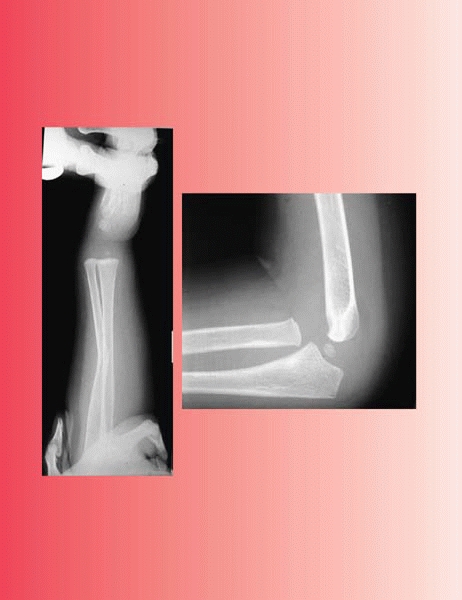

subtle injury. The most common and most important oversight is the

missed Monteggia fracture, especially in the apparently isolated ulna

injury. To stay out of trouble, the orthopaedist should insist on two

views of the entire forearm at right angles to one another, as well as

dedicated films of the elbow, to be assured that the radiocapitellar

relationship is satisfactory (Fig. 7-7). To

![]() |

|

▪ FIGURE 7-7 A missed Monteggia fracture presented 2 weeks after injury. All images done at the outside hospital (A,B)

showed only a greenstick fracture of the ulna, and mom’s hand covering the elbow. Suspicious for a Monteggia, we removed the cast and obtained good elbow images, revealing the dislocated radial head (C,D). |